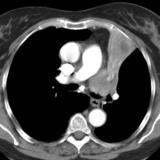

LUL Collapse Case 1 CT 4in1

Date: 02/19/2004

Views: 3518